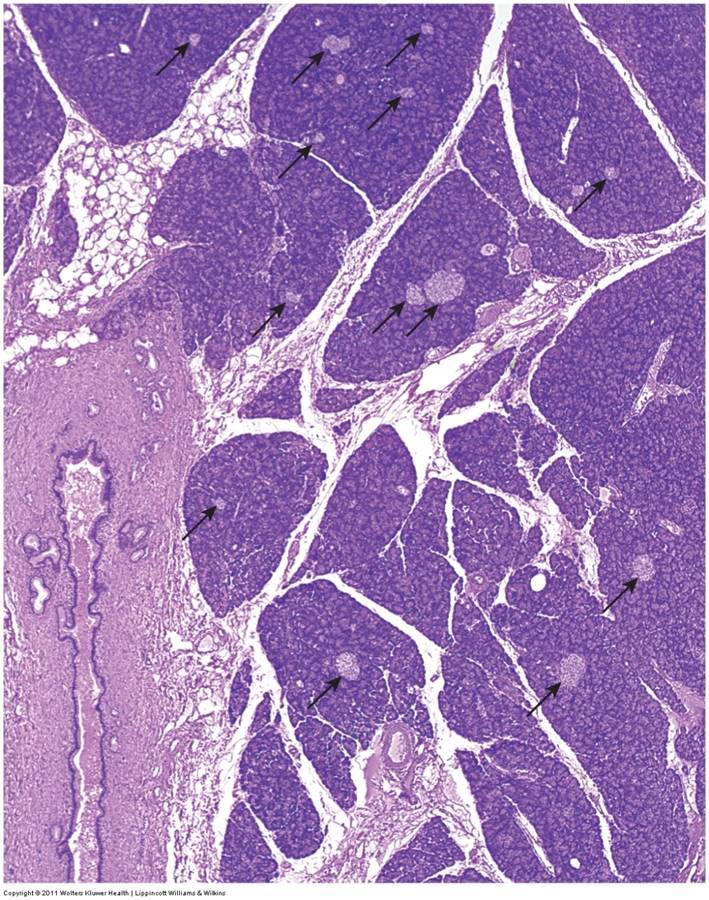

What do the arrows indicate?

Islets of langerhans

What type of pancreatic tissue is this?

Endocrine tissue